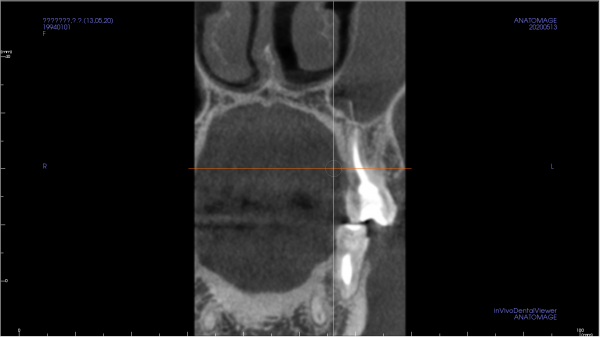

На КТ снимке просматривается затемнение левой верхнечелюстной пазухи, а также небольшой узкий тяж, идущий от четверки. Ранее проводилась операция по удалению кисты и резекции верхушки корня на двойке.

Может ли так просматриваться корень зуба и корень ли это? Насколько опасно наличие этого тяжа в пазухе?

По этому срезу диагностировать проблему невозможно. Обратитесь к хирургу на приём.